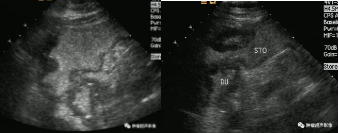

左图:胃淋巴瘤:胃壁弥漫性增厚但是胃腔未见明显狭窄

右图:胃癌:幽门及胃窦部狭窄明显